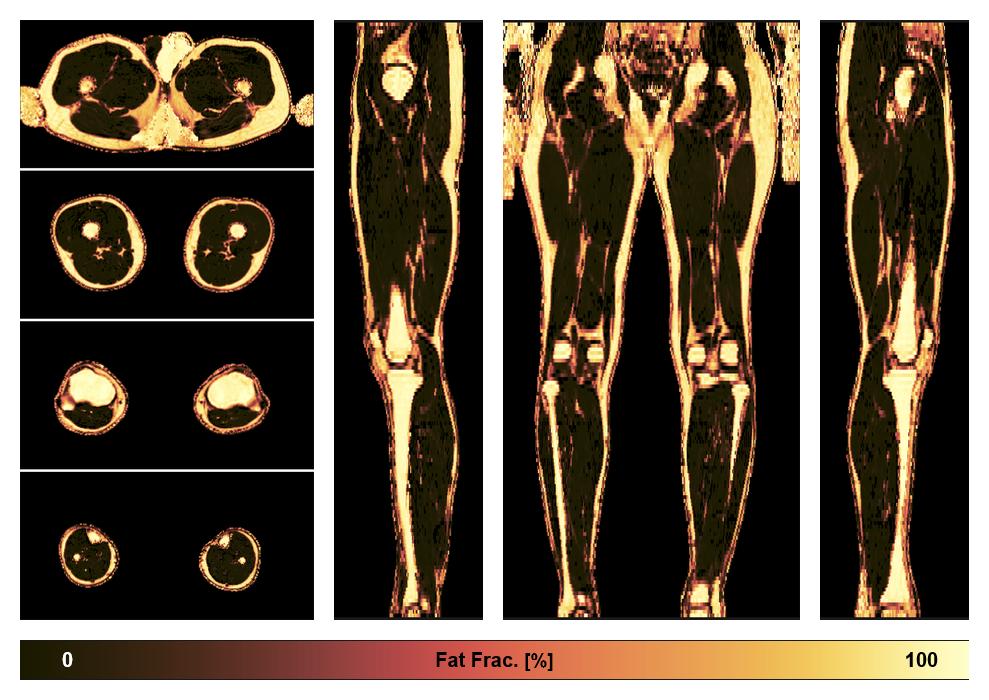

• Fat fraction

The fat fraction of the lower extremity obtained from the dixon reconstruction for muscle water fat quantification.